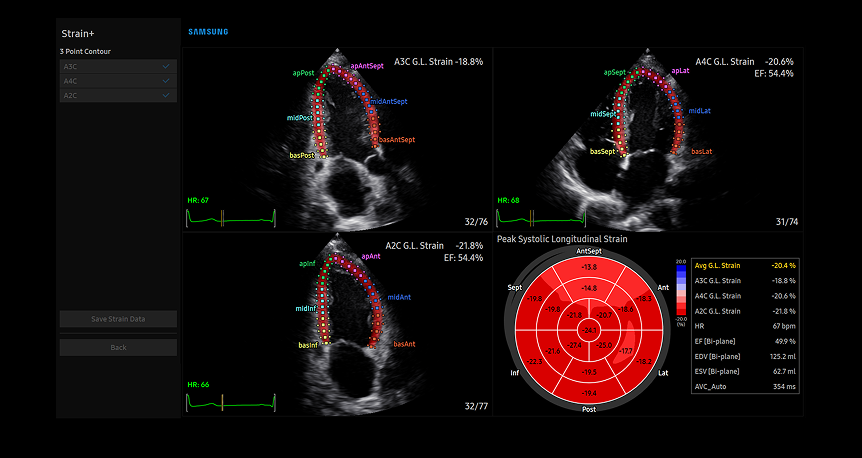

Strain+1 LV

Advanced Strain+ LV cardiac analysis on Samsung's diagnostic display showing multi-view heart chamber assessment with color-coded ventricular wall tracking and comprehensive bull's-eye plot visualization

Strain+ è uno strumento quantitativo per misurare il movimento della parete globale e segmentale del ventricolo sinistro (LV), dell'atrio sinistro (LA), di e del ventricolo destro (RV) per la funzione sistolica e diastolica del cuore.